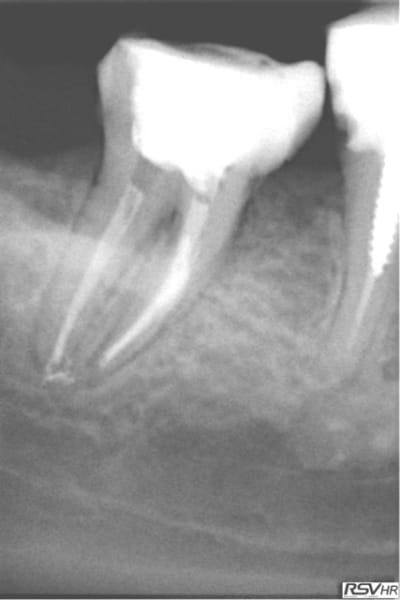

Ce sont des cones dentsply mais pas les réciprocs. je les scelle au tubuli seal en pompant un peu ( d'ailleurs sur la 25 ci dessous qui avait un 4eme ca a fait un dépassement preuve que ca fuse) je les coupe ensuite au système B avec le pluggeur qui sert à faire le bouchon apical.

Tres pratique d'ailleurs pour faire le cas échéant les tenons dans la séance de l'endo, l'empreinte et la provisoire dans la foulée.

Tu as fait des progrès. Disons par exemple que sur la deuxième prémolaire, tu es allé un poil trop loin, ce qui a réduit sérieusement la constriction apicale. Peut être que que tu mesures ta LT un demi millimètre plus longue que nécessaire.